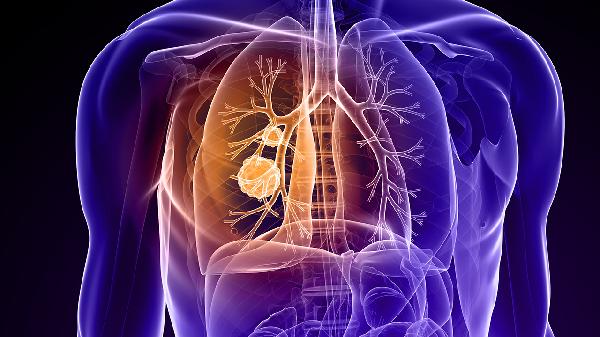

不吸烟也会得肺癌?这可不是危言耸听!隔壁小区王阿姨一辈子没碰过香烟,却在体检时查出早期肺癌。很多人以为只要远离烟草就能高枕无忧,其实生活中隐藏的"隐形杀手"更值得警惕。今天就带大家认识这些容易被忽视的危险因素,学会保护自己的肺。

预防肺癌不能只盯着吸烟这件事。改善厨房通风、远离二手烟、做好职业防护、关注家族病史,这些细节才是守护肺部健康的关键。建议40岁以上人群每年做一次低剂量CT筛查,特别是长期接触危险因素的高危人群。记住,早发现早干预,肺癌的治疗几率可以大大提高。从今天开始,给你的肺多1点关爱吧!